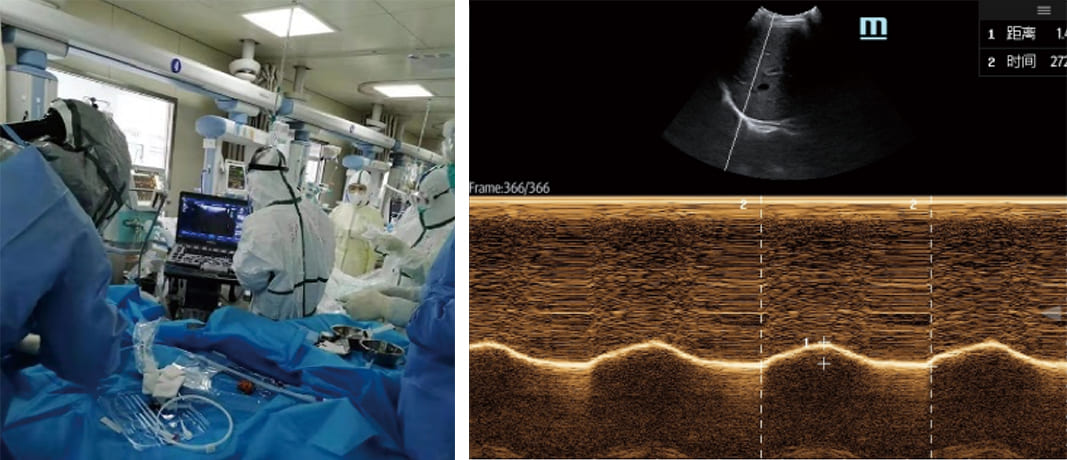

2. Mechanical Ventilation Support

For patients requiring mechanical ventilation, precision is of paramount importance. Portable ultrasound devices have stepped up to assist in this critical task. They can measure the airway diameter limit, aiding clinicians in selecting the appropriate ventilation tube diameter. Moreover, they provide the means to observe the movement of the diaphragm and guide the ventilator offline. This feature enhances patient safety and ensures that mechanical ventilation is optimized to meet individual patient needs.

Furthermore, the ability to support mechanical ventilation with accurate airway measurements and diaphragm monitoring is of paramount importance. In cases of respiratory failure, precision is the key to successful ventilation management. Portable ultrasound devices provide this precision, ultimately improving patient outcomes.